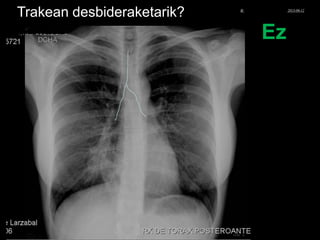

Trakean desbideraketarik?

Ez